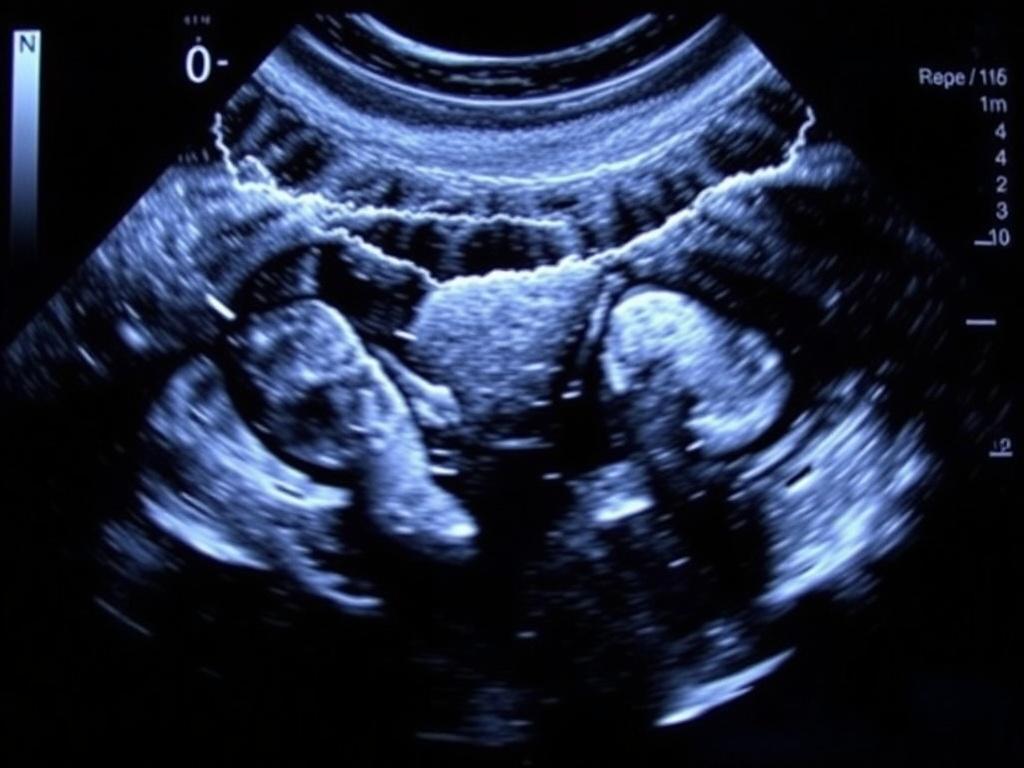

3D и 4D УЗИ чаще используются в акушерстве и в маммологии. 3D даёт объёмную картинку, 4D — объёмное изображение в движении. Это красиво и удобно для визуализации структур, но не всегда является медицинской необходимостью.

В акушерстве УЗИ помогает следить за развитием плода, оценивать плаценту и количество околоплодных вод. Но окончательные клинические решения принимает лечащий врач, опираясь на картину в целом.